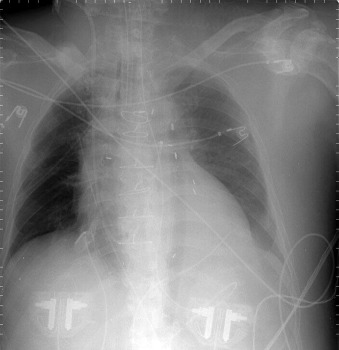

Pulsatile Devices: Intra-aortic Counterpulsation Balloon ( Figs. 24-1 to 24-7 )

The tip of an intra-aortic balloon (which is highly visible because of its metallic marker) should be at least 4 cm below the “knuckle” of the aorta (i.e., below the left subclavian artery). The balloon appears as a cylindrical lucency if the radiographic exposure happened to be while it was inflated in diastole. Widening or haziness of the aorta suggests aortic dissection as a complication of the catheter. Incorrect insertion into the inferior vena cava is suggested by the shadow of the catheter lying to the right of the patient’s vertebral column.